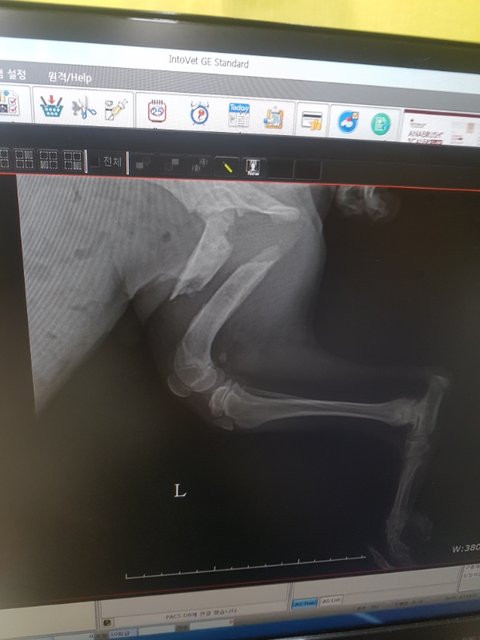

올때부터 뒷다리를 들고있었고 여기저기 상처투성이 였습니다

엑스레이상 뒷다리가 똑 부러져있습니다

사진을 보는것만으로도 아이의 고통이 전해져 명치끝이 아파옵니다